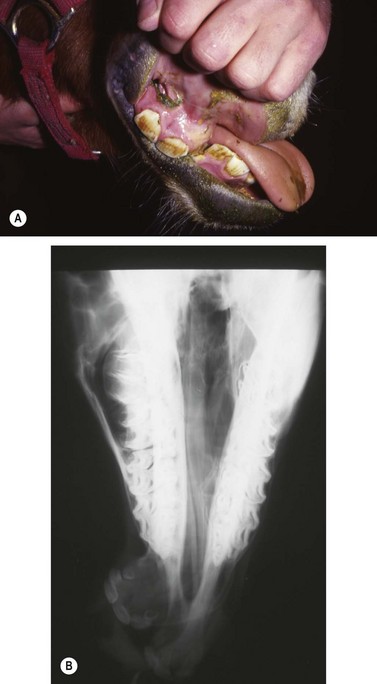

The most common indication for partial mandibulectomy is to remove a neoplastic lesion of the rostral aspect of the mandible. The most commonly encountered mandibular neoplasm is the juvenile ossifying fibroma, and this neoplasm is most commonly found on the mentum (Fig. 19.24). Consequently, the mentum is that portion of the mandible that is most frequently amputated. Other neoplasms sometimes encountered on the mentum include the carcinoma (Fig. 19.25) and ameloblastoma. Another indication for amputation of the rostral aspect of the mandible is fracture of the mentum not amenable to repair.

image

Fig. 19.24 The juvenile ossifying fibroma is the most commonly encountered mandibular neoplasm and is most commonly found on the mentum.

Fig. 19.25 Laterolateral radiograph of the skull of a horse with a carcinoma of the mandible. The rostral portion of the mandible of this horse was amputated caudal to the symphysis.